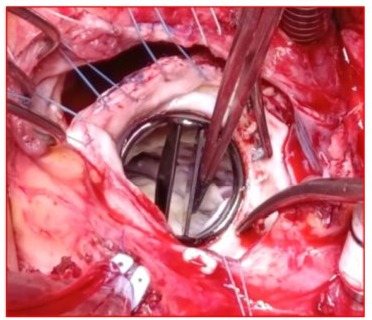

Intraoperative assessment showed replacement unnecessary. Adequate oxygen delivery and extraction confirmed. Hematocrit: 20, transfused 2 units of red blood cells. MAP maintained at 65-75 mm Hg. Left atrium closed, DE bubbling for venting cardiac chambers. Aorta unclamped, continuous venting, electrodes placed, spontaneous defibrillation. Clamping duration: 90 mins. Heart loaded; ventilation resumed after TEE control. Weaned from CPB with gradual pump flow reduction and resumed ventilation. Cardiac function restored under dobutamine at 5 µg/kg/min and norepinephrine at 2 µg/kg/min, initial sinus rhythm: 80 bpm. Right atrial DE cannulation performed, blood retrieved from reservoir via aortic cannula due to hypovolemia observed on TEE. Heparin antagonized with protamine in a 1:1 ratio, aortic cannula removed. Hemostasis checked before closing thoracic cage. Drains inserted before closing sternum with steel wires. Skin closed with absorbable sutures. CPB duration: 125 mins. Post-CPB TEE under dobutamine at 4 µg/kg/min and norepinephrine at 2 µg/kg/min showed good mitral valve functionality, good LV contractility, improved subaortic velocities, and high filling pressures. (Video 10) (Figure 10).

Figure 10: Postoperative continuous Doppler TEE on the mechanical mitral valve after weaning from CPB, showing a low mean gradient measured at 3 mm Hg following cleaning of the valve.

Figure 13: Postoperative continuous Doppler TEE on the mechanical mitral valve 1 hour after weaning from CPB, showing a mean gradient of approximately 4 mm Hg, with a mitral valve area of around 22 mmHg.

Figure 14: Postoperative pulsed Doppler TEE after weaning from CPB on the mechanical mitral valve showing an antegrade mitral flow velocity of the E wave at 2 m/s (>1.5 m/s) and an E/A ratio of 4.96, indicating elevated filling pressures in the absence of an A wave due to atrial fibrillation.